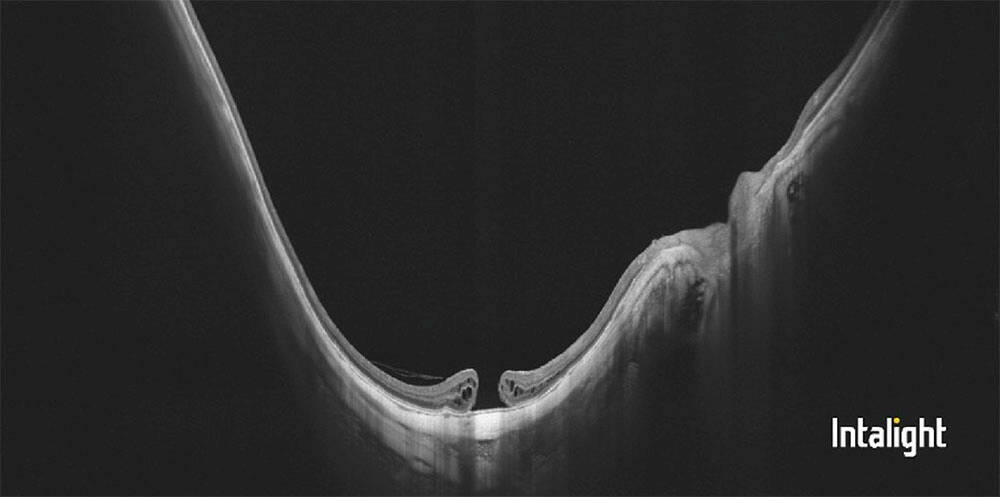

Figure 2. Patiente de 26 ans présentant une baisse d’acuité visuelle avec un décollement séreux rétinien hémorragique visible à l’OCT (A, tête de flèche). Les temps tardifs de l’angiographie à la fluorescéine ne montrent aucune diffusion (B) et la rupture de la membrane de Bruch est hypofluorescente sur le temps tardif de l’angiographie au vert d’indocyanine (C). L’OCT-A segmentée sur la rétine externe ne montre aucun signal vasculaire (D).